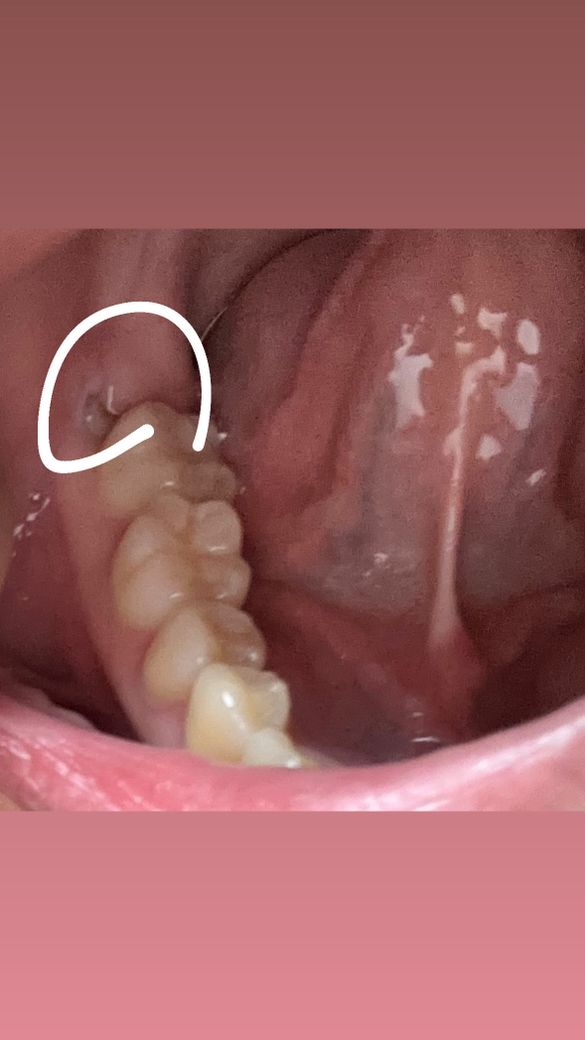

안녕하세요 왼쪽 매복 사랑니를 아직 안뽑았는데 이거 얼른 뽑아야 하는 경우인가요 ?̊̈

왼쪽은 아팠다 안아팠다 하는데 요즘 아예 안아팠거든요 근데 어제 갑자기 뭔가 따갑길래 보니 왼쪽 매복사랑니쪽이 하얗게 뭐가 올라와서 확인해보니까 이빨같아요 이런경우가 처음이라 걱정인데 ㅠㅠ 이렇게 올라온경우 얼른 뽑아야 하나요 ?̊̈ 6월 공휴일 지나고 나서 뽑을 예정이였는데... 아니면 6월 7일이나요... 그때까지 둬도 괜찮나요 ?̊̈ 아님 이번주에 뽑아야 하나요 ?̊̈

• 1번 째 사진

네 매복된 사랑니 맞습니다

사랑니가 뒤늦게 올라온다기보다는 덮여있는 잇몸이 들쳐지면서 사랑니가 일부 드러난 것 같습니다

해당 부위 불편 시 사랑니 발치해주시면 됩니다.